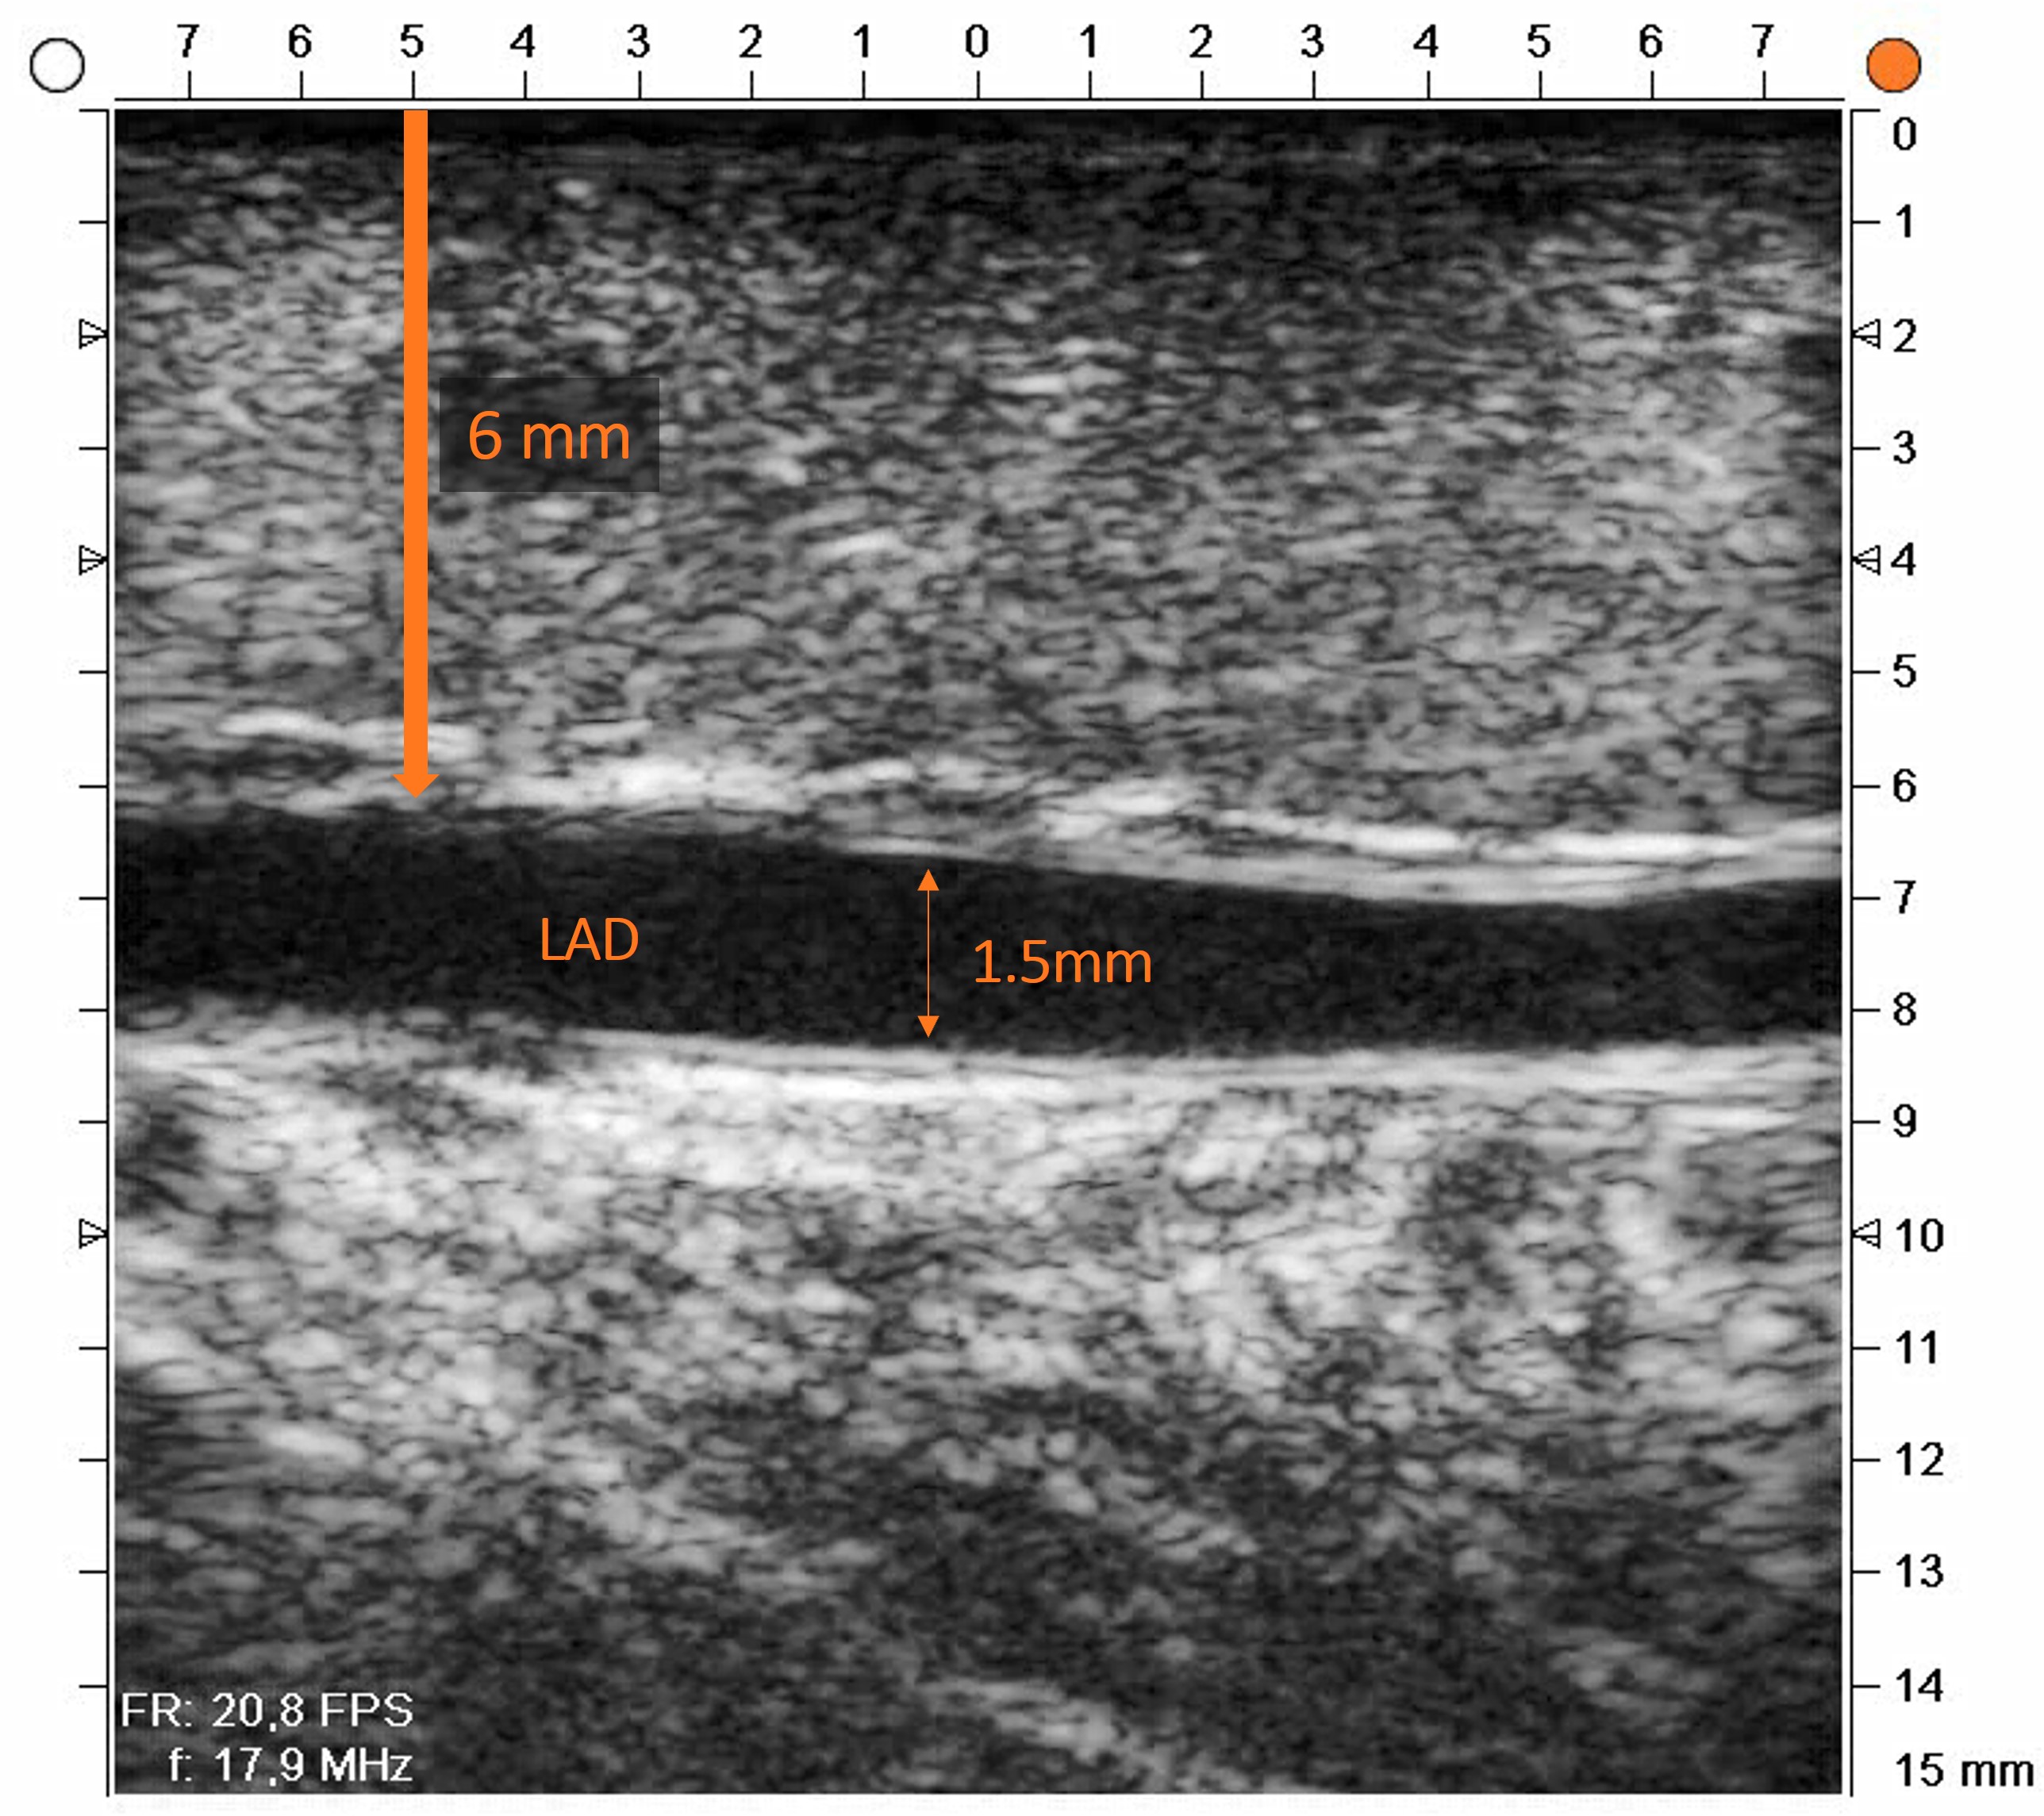

REQUEST Study - LAD at 6 mm depth. Clean walls. A confident anastomosis.

In this case from the REQUEST Study, the target site was an intramural LAD. The surgeon scanned the vessel before incision using the Medistim L15 high-frequency ultrasound imaging probe and the anatomy became immediately clear.

Patient & Imaging Summary

• Patient: 80-year-old male

• BMI: 25.6

• Target vessel: Intramural LAD

• Depth detected: ~6 mm (proximal wall)

• Lumen diameter: ≥ 1.5 mm

• Vessel wall: Clean, no plaque or calcification

• HFUS localised the LAD at 6 mm depth - a vessel that would have been missed or required blind dissection without imaging.

• Lumen diameter ≥ 1.5 mm and clean vessel walls confirmed this was an ideal anastomotic site - no surprises at the time of incision.

Intramural LAD at 6 mm depth